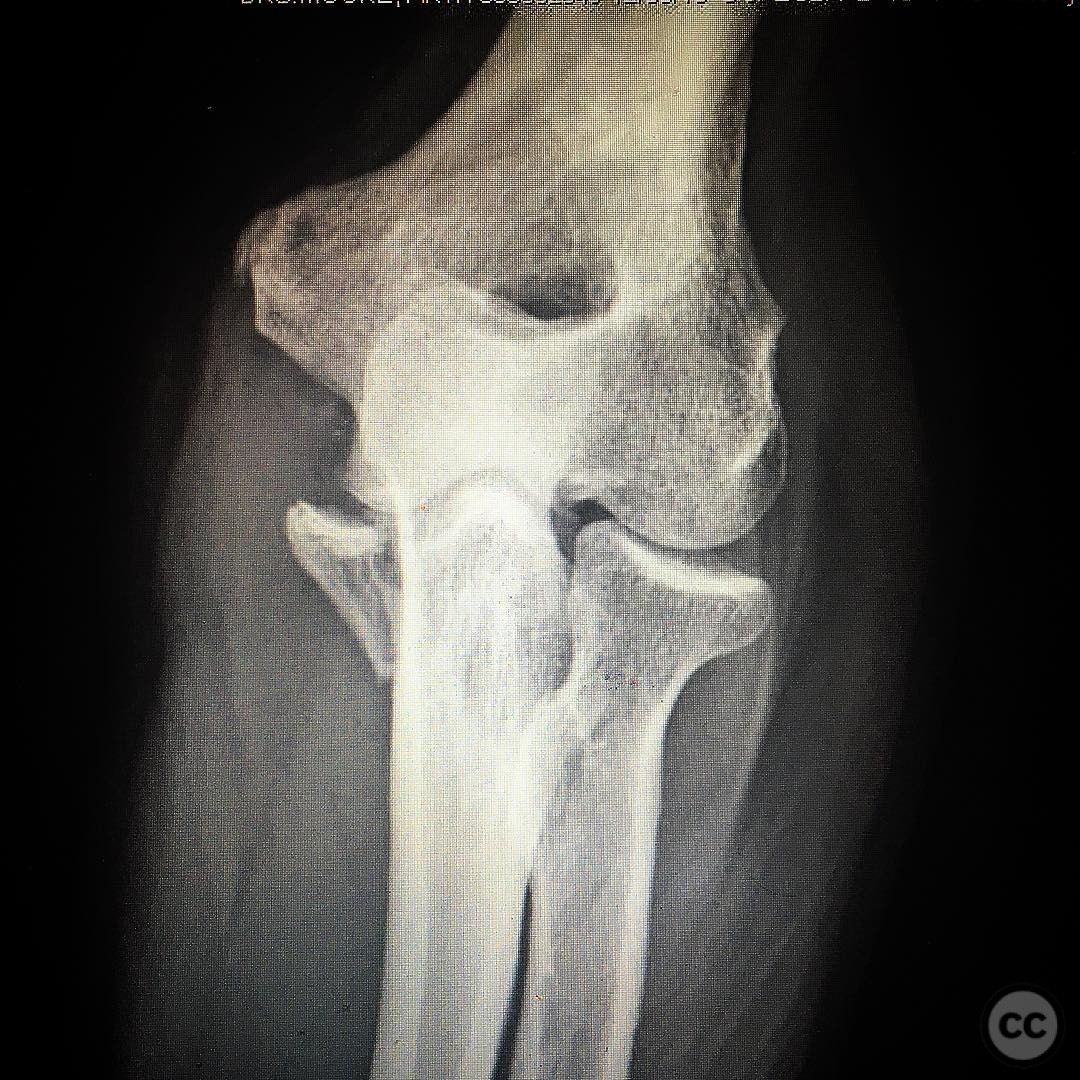

By Benedikt Abels

Schatzker type B olecranon fracture

Schleswig-Holstein, Germany

Ulna - AO/OTA 2Ux